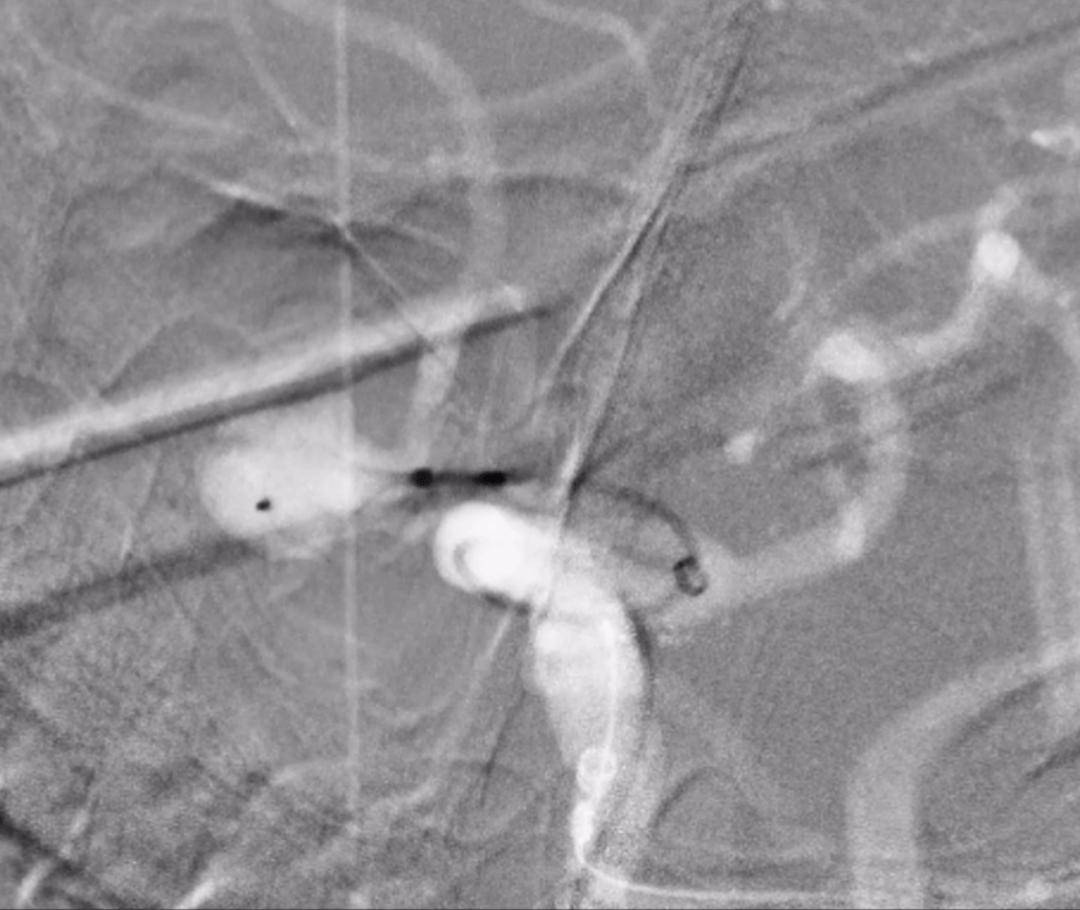

基于解剖学参数,AI辅助系统进行了高拟真的“手术预演”。它模拟了不同型号的扰流装置在血管模型中的释放过程,辅助医生筛选出更匹配的装置型号,并推演装置释放后的形态和位置。屏幕上,医疗团队可以清晰看到装置将如何放置,才能有效改变动脉瘤内的血流,同时保护所有分支血管。

这意味着,在真正手术开始前,一场周密的数字规划已经完成。霍晓川主任团队在审核全部分析与模拟结果后,最终敲定了手术方案。

图5-7:扰流装置释放过程、释放结束、术后造影